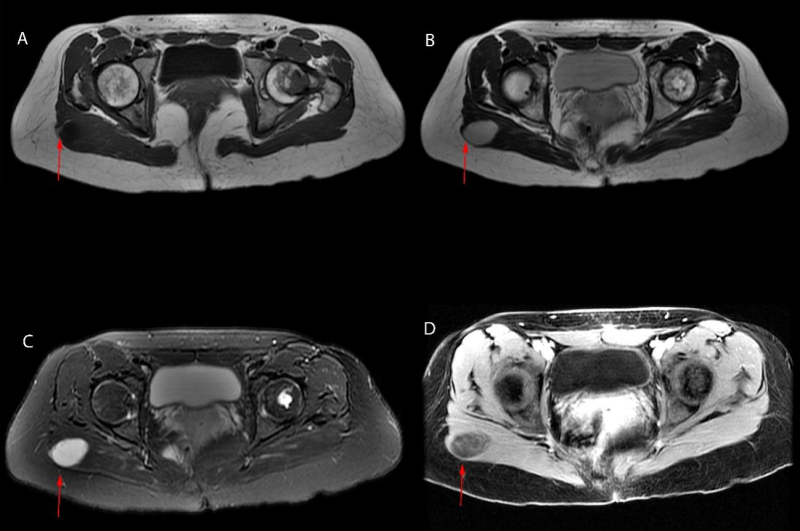

La resonancia magnética (RM) de cadera demostró una lesión ovalada localizada en el músculo glúteo mayor derecho en su región más superficial y externa, de 3,3 x 2,6 x 3,9 cm (fig. 2, flechas rojas). La secuencia T1 (A) mostró lesión hipointensa, con el anillo graso característico de los mixomas alrededor de la lesión. En la secuencia T2 (B) la lesión fue hiperintensa, y en la secuencia T2 (C) con supresión grasa la lesión fue también hiperintensa. Después de la administración de gadolinio, se demostró realce difuso (D). En el fémur izquierdo se observó una lesión endomedular bien definida con borde esclerótico, compatible con la displasia fibrosa conocida. Se realizó biopsia con aguja gruesa guiada por ultrasonido de la masa glútea; el resultado fue compatible con mixoma.